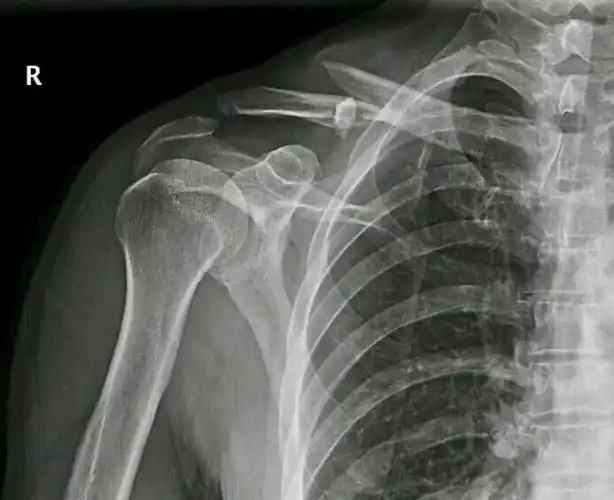

锁骨骨折